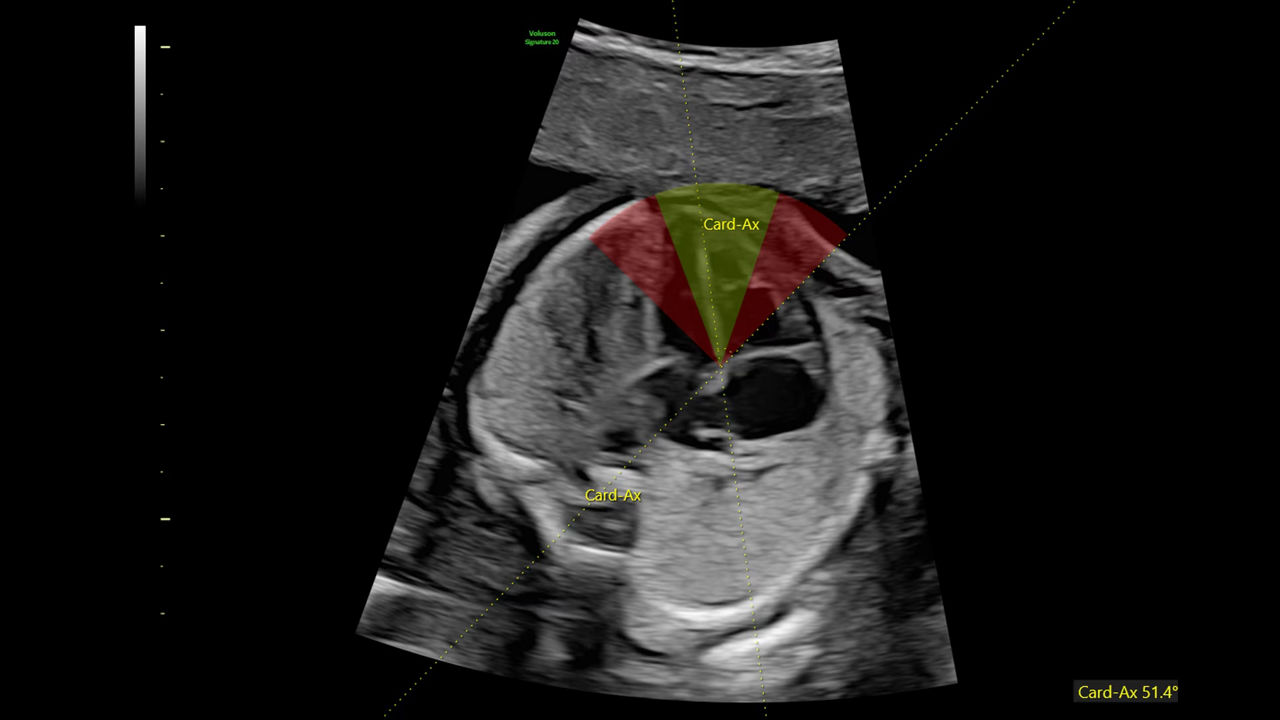

Next level color Doppler that delivers exceptional sensitivity for easy, fast visualization of blood flow, displaying a 3D like appearance as seen in this 27-week fetal heart.